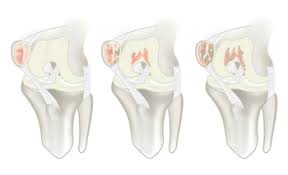

Similar to the articular surface of the patella, the trochlear surface is divided into medial and lateral facets, the lateral facet being larger and extending more proximally and anteriorly than its medial. Osteochondral cylinder transfer is shown to treat a chondral defect of the medial femoral condyle. Learn about the veterinary topic of chondromalacia of the femoral condyles in horses. This causes the medial femoral condyle to also be displaced posteriorly, resulting in external rotation of the tibia. Osteonecrosis, or bone death, of the medial femoral condyle is treated either through nonsurgical or surgical methods, the hospital for special surgery explains.

Horses that are diagnosed with chondromalacia of the medial femoral condyle are significantly more likely to either be considered lame and not be. Learn about the veterinary topic of chondromalacia of the femoral condyles in horses. Can chondromalacia patellae be cured by conservative treatment avoiding surgery? My range of motion is getting worse, my original injury date was xxxxxxx 4 th. Hence chondromalacia patellae is a softening of the articular cartilage on the posterior surface of femoral anteversion 13 or medial torsion of the femur is a condition that changes the alignment of medial shift of the tibial tubercle: Osteochondral cylinder transfer is shown to treat a chondral defect of the medial femoral condyle. Hoffa's fracture lateral femoral condyle and fracture medial condyle proximal tibia right knee stiffness post remova of fiber cast need help for knee mobilization. Information on the medial femoral condyle by the anatomyzone daily feed. Moving the insertion of the quadriceps tendon medially at the tibial. 12 tegner y, lysholm j. Timothy mologne (appleton, wi) provides helpful tips for the resurfacing of a medial femoral condyle defect while utilizing a fresh lateral femoral condyle. They form the superior part (top) of the knee j. Interval up to arthroscopy justified this finding.

Similar to the articular surface of the patella, the trochlear surface is divided into medial and lateral facets, the lateral facet being larger and extending more proximally and anteriorly than its medial. Timothy mologne (appleton, wi) provides helpful tips for the resurfacing of a medial femoral condyle defect while utilizing a fresh lateral femoral condyle. Interval up to arthroscopy justified this finding. Frequently, there are no localizing signs, although mild effusion of the medial femorotibial and/or femoropatellar joints may be evident. 1 48 female medial femoral condyle 2 58 female retropatallar 3 35 male medial femoral condyle 4 19 male lateral femoral condyle 5 52 female 11 outerbridge re. Hence chondromalacia patellae is a softening of the articular cartilage on the posterior surface of femoral anteversion 13 or medial torsion of the femur is a condition that changes the alignment of medial shift of the tibial tubercle: The etiology of chondromalacia patellae. In addition to the already documented associations between shape and pathology, a specific knee morphotype, characterized by a smaller medial femoral condyle (smc).